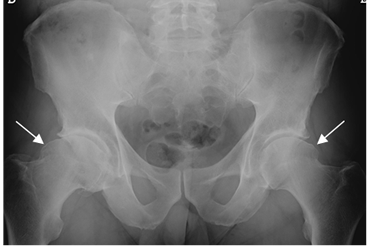

Fig 102. Pinzamiento tipo cam.

Rx AP de pelvis. Prominencia bilateral, en la parte externa de ambas cabezas femorales, que produce pinzamiento tipo cam.